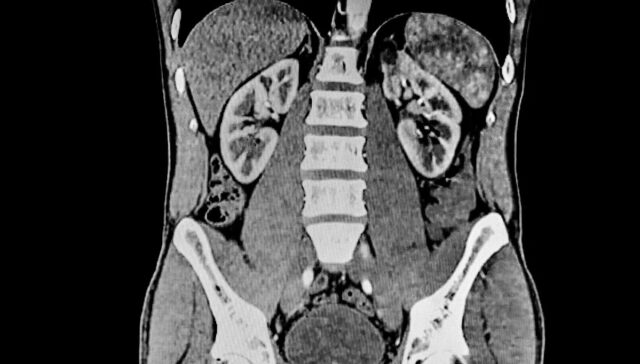

Também foi descoberto que as propriedades físico-químicas da poliamida influenciam a forma como ela é distribuída no corpo após a ingestão, com o microplástico se acumulando em órgãos como o fígado.